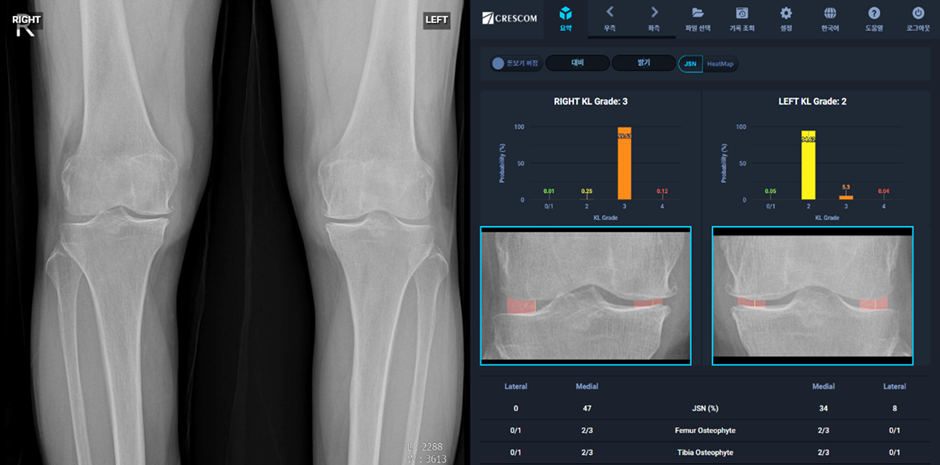

최근 인공지능 기술의 발전으로 인해 무릎 정렬 상태와 관절염의 상관관계를 보다 정밀하게 분석할 수 있는 연구가 활발히 진행되고 있다. AI 기반 연구는 주로 딥러닝 및 머신러닝 기법을 활용하여 방대한 의료 데이터를 분석하고, 특정 패턴을 도출하는 방식으로 이루어진다.

3.1 AI 기반 영상 분석

MRI, X-ray 등의 의료 영상 데이터를 AI로 분석하면 무릎 정렬 상태를 정밀하게 측정할 수 있으며, 이를 통해 관절염의 진행 단계를 예측하는 것이 가능해진다. 딥러닝 알고리즘을 이용하면 정상 정렬과 비정상 정렬을 자동으로 분류하고, 관절염 발생 위험을 정량적으로 평가할 수 있다.

3.2 AI를 활용한 관절염 진행 예측

AI는 과거의 의료 데이터를 학습하여 향후 관절염이 어떻게 진행될지를 예측하는 데 도움을 줄 수 있다. 예를 들어, 특정 무릎 정렬을 가진 환자가 몇 년 후 관절염이 어느 정도 심화될지를 AI 모델이 예측함으로써 조기 치료 및 예방 전략을 수립하는 데 기여할 수 있다.